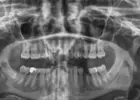

Çene Kistleri

Implant tedavisi